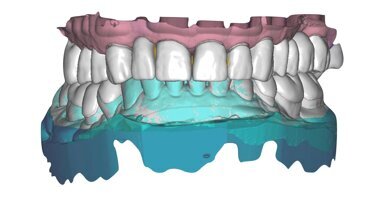

Lo strato iniziale era il guscio linguale, creato a mano libera per i denti 11 e 21 con l’uso di una matrice Mylar. Sarebbe stato più facile creare lo strato iniziale mediante l’uso di una mascherina in putty realizzata da una ceratura diagnostica, ma il paziente ha scelto di omettere questo passaggio a causa di limiti economici. Lo strato iniziale era spesso circa 0,3 mm, ristabiliva la lunghezza e le proporzioni desiderate del dente, ed è stato realizzato con una tinta smalto traslucente bianco latte. Per questa struttura è stato utilizzato Amaris (VOCO) nella tinta TN (translucent neutral).

L’obiettivo dello strato successivo era quello di iniziare a mascherare il più possibile lo sfondo traslucente con tinte dentina opache. L’opacità sarebbe stata applicata in modo da bloccare la visibilità delle linee di giunzione. Il non ottenimento di ciò avrebbe portato a un risultato finale meno estetico. In questo caso, il limite era lo spessore e la traslucenza del nucleo residuo a causa dei materiali usati in passato.

È stato utilizzato Amaris O3 (Opaque #3) nella regione disto-assiale negli strati più profondi per visualizzare se questa tinta fosse adeguata per corrispondere al colore del nucleo del dente. Dopo la polimerizzazione, si è deciso di utilizzare negli strati superficiali una tinta opaca leggermente più chiara (Opaque #2) per meglio ottenere il valore desiderato del dente. Questa modificabilità matematica di Amaris rende soddisfazione eseguire restauri dentali estetici. Questo strato è importante anche perché la dentina crea la tinta base del dente e si pone a complemento della fluorescenza e dell’interpretazione cromatica del restauro finale4.

Lo strato di dentina superficiale è stato modellato e sagomato cervicalmente nelle aree marginali per chiudere la regione della perforazione subgengivale buccale. La metà incisale è stata realizzata mediante un secondo incremento di Amaris O2 e modellata incisalmente. Questo strato è caratterizzato da strisce irregolari dei dentina che formeranno le basi degli effetti incisali visibili nel risultato finale. Anche la formazione del lobo dello strato di dentina viene realizzata in questo strato dentinale superficiale prima della polimerizzazione finale. Lo strato successivo prevede una tinta altamente traslucente utilizzata nelle aree incisali e del lobo dentinale come riempitivo di spazi. L’uso di una tinta traslucente trasparente aumenta la penetrazione, la trasmissione, la riflessione e rifrazione della luce in quest’area del risultato finale.

La tinta viene ora valutata con il colore disidratato dei denti adiacenti. È essenziale che una volta decisa la mappa del colore, vi siano poche modifiche intraoperatorie, se non addirittura nessuna. L’aspetto più chiaro dei denti disidratati è un grande elemento ingannevole, che porta i clinici a creare denti che risulteranno poi troppo bianchi una volta che la dentizione adiacente si sarà reidratata. In questo caso, il paziente aveva richiesto denti leggermente più chiari in quanto in futuro intendeva sottoporsi allo sbiancamento dei denti vitali adiacenti. Dato che gli incisivi centrali in natura sono spesso una frazione più chiara degli incisivi laterali, è stato deciso di applicare una tinta smalto più chiara (TL: translucent light) invece di quella pianificata (TN: translucent neutral). Ancora una volta, questa modificabilità matematica di Amaris permette il controllo del valore del prodotto finale nelle diverse fasi della ricostruzione.

Per quanto riguarda la scala colori intraoperatoria, vi sono due sfere di composito Amaris polimerizzato applicate sul dente 11: quella posizionata più incisale è la tinta TN (translucent neutral), e quella più cervicale è la tinta TL (translucent light). La tinta TL applicata in uno strato spesso aumenterebbe il valore del dente oltre la tinta desiderata, quindi è importante giudicare sempre lo spessore e la morfologia degli strati di dentina dall’aspetto incisale1. In questo caso, uno strato molto sottile di tinta smalto era ciò che serviva a realizzare il profilo di emergenza del dente e gli angoli lineari al profilo completo, e quindi è stato deciso di utilizzare la tinta TL per aumentare leggermente il valore dello strato di dentina.